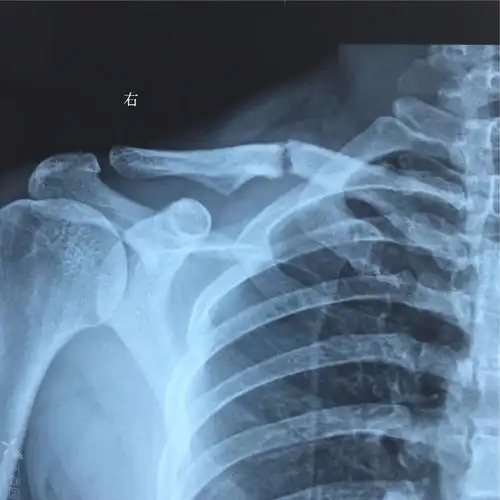

锁骨远端骨折一百天复查患者要求手术

锁骨骨折

锁骨x光片